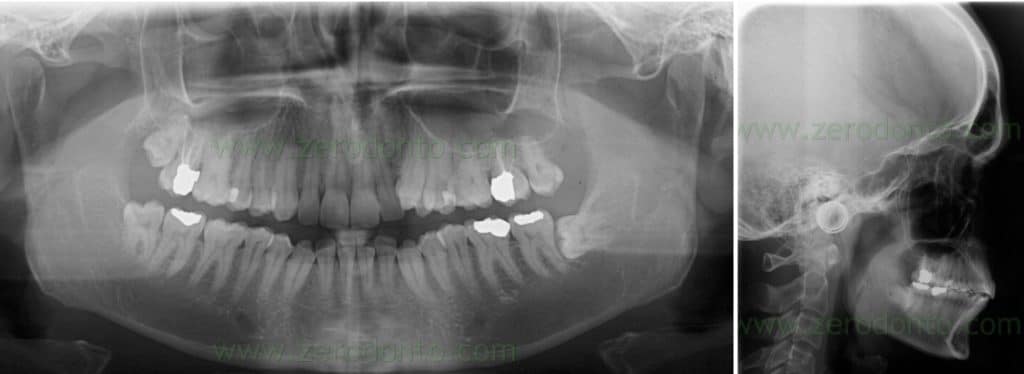

The orthopantomography showed:

- teeth 17 and 27 previous root canal therapies

- teeth 47, 36, 37 extensive reconstructions

- impacted teeth 38

The cephalometric tracing was carried out by identifying 17 landmarks that evaluated dental, skeletal and soft tissues changes. A perpendicular line was drawn to the SN plane from the intersection of the anterior wall of sella turcica and the anterior cli- noid processes in order to form a vertical reference line.

The stability of these landmarks is widely documented in literature.

Cephalometric landmarks and skeletal measurements. Landmarks: S, sella; Sa, intersection of the anterior wall of sella turcica and the anterior clinoid processes; Na, nasion; Or, orbitale; Po, porion; A, A point; B, B point; Go, gonion; UL, most anterior point of the upper lip; LL, most anterior point of the lower lip; u6f, furcation point of the upper first molar; u6s, sulcus between buccal tubercules of the upper first molar; u5b, tip of the buccal cusp of the upper second premolar; u4b, tip of the buccal cusp of the upper first premolar; U1i, incisal edge of the upper central incisor; L1i, incisal edge of the lower central incisor. SV indicates vertical reference line. Skeletal measurements: 1, SNA; 2, SNB; 3, ANB; 4, Go-Gn SN; 5, FMA; 6, UL – SV; 7, LL – SV. B, dental angular measurements (o): 1, U1-SN; 2, U4-SN; 3, U5-SN; 4, U6-SN. Dental linear Measurements (mm): 5, U6 – SN; 6, U1 – SV; 7, U4 – SV; 8, U5 – SV; 9, U6 – SV.

Final orthopantomography

Final teleradiography Cephalometric tracing